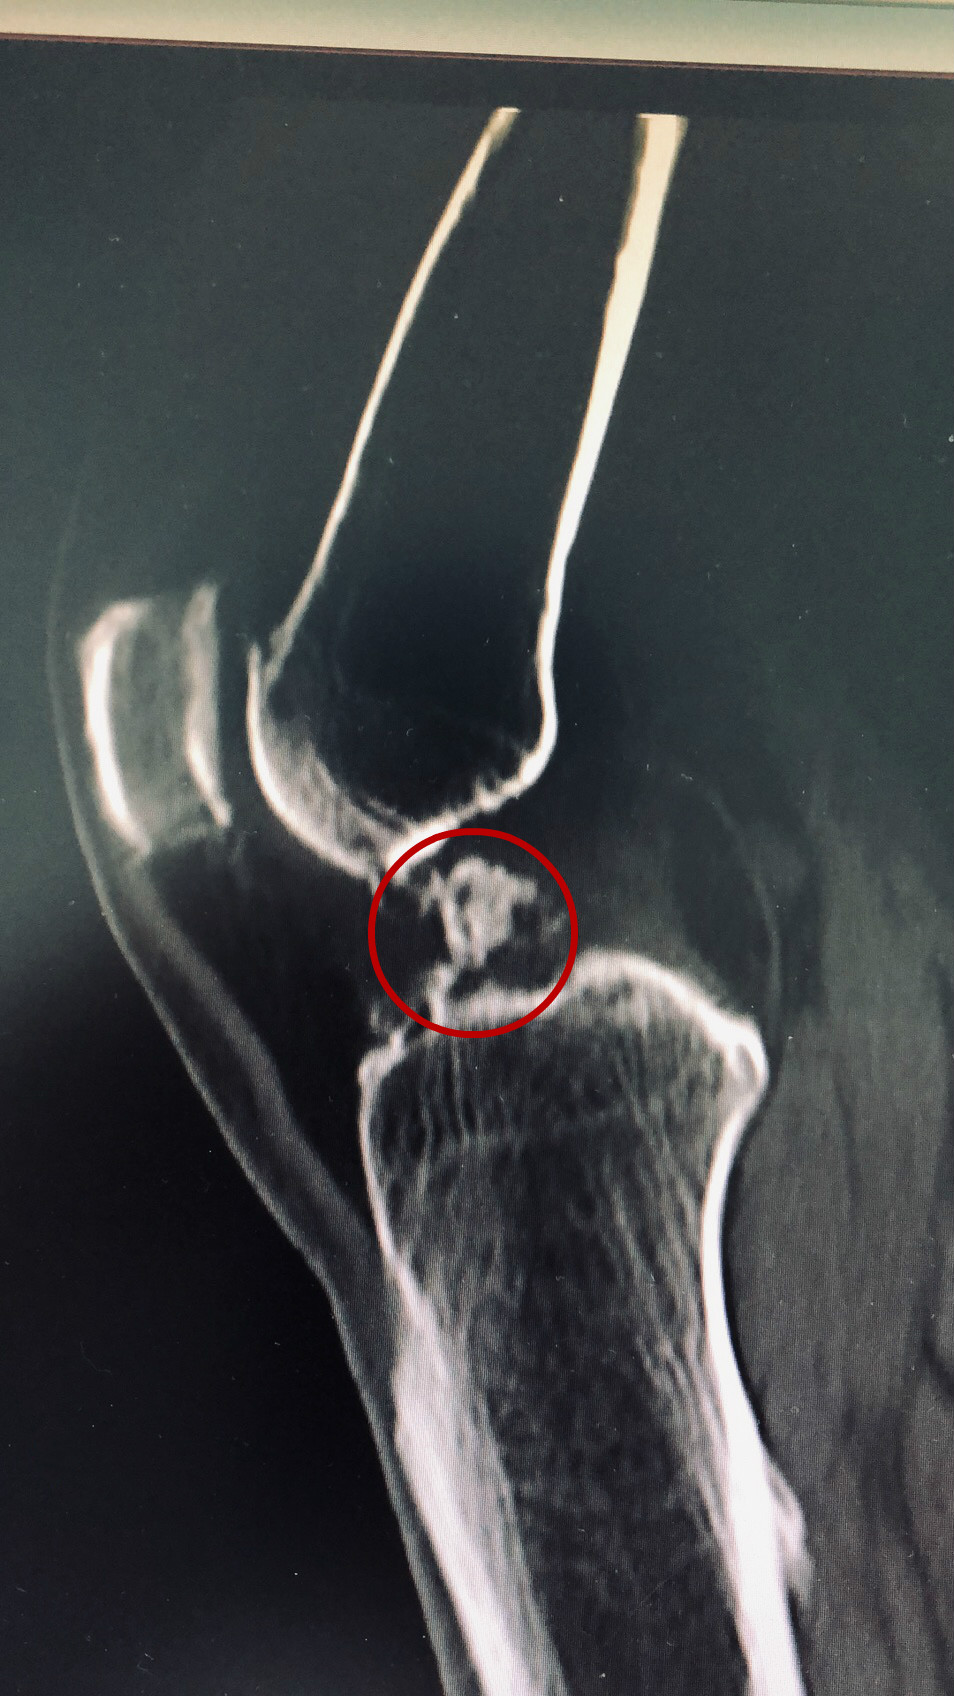

2016年初,王女士突然发现自己的右膝关节肿胀的厉害,走不上半里路就觉得膝盖隐隐作痛,里面像是有什么东西卡住了似的,硌的生疼。症状持续性不缓解四个月后,王女士腿脚变得越来越不利索,站着难蹲下、蹲下站不起,只能借助拐杖行走。到医院检查后,王女士被诊断为右膝关节退行性病变,右膝关节腔见多发游离体,就像是有一个个“小石子”跑进膝关节里卡住了,需手术摘除治疗。但由于王女士心脏冠脉堵塞接近80%,伴有“三高”等多种疾病,且血糖控制不佳,常规腰麻风险较大,最终放弃了手术治疗。

术前图

经过一段时间的住院治疗,王女士膝关节疼痛虽然得到有效缓解,但由于她的“小石子”仍然紧紧卡压在股骨髁间窝,几乎是“长”在里面了,导致关节呈屈曲状态,始终无法正常行走。

住院期间,骨伤二科主治医师覃剑、梅凌多次与王女士交流沟通,为其详细讲解手术过程。在成功消除患者心理恐惧后,近日王女士接受了局麻微创关节镜手术治疗,术中从膝关节腔取出2个蚕豆大小游离体。术后,王女士恢复良好,第二天即可下床行走,右膝关节正常屈伸。经过一段时间的住院调理,5.25日王女士已顺利出院回家休养。